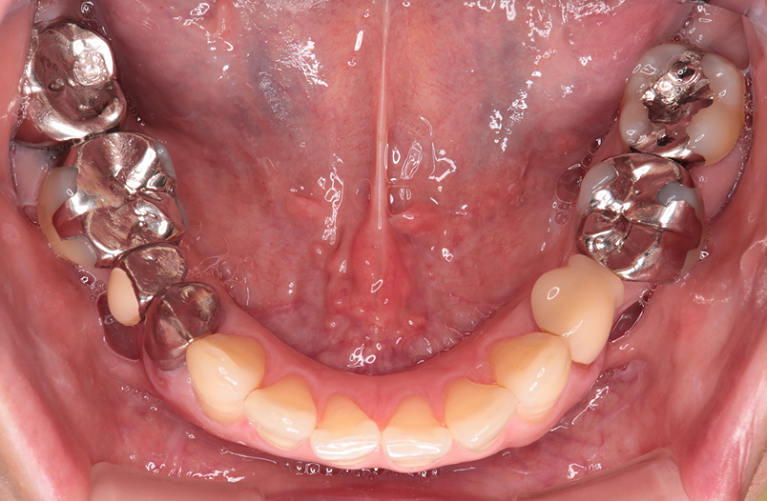

治療前

下顎